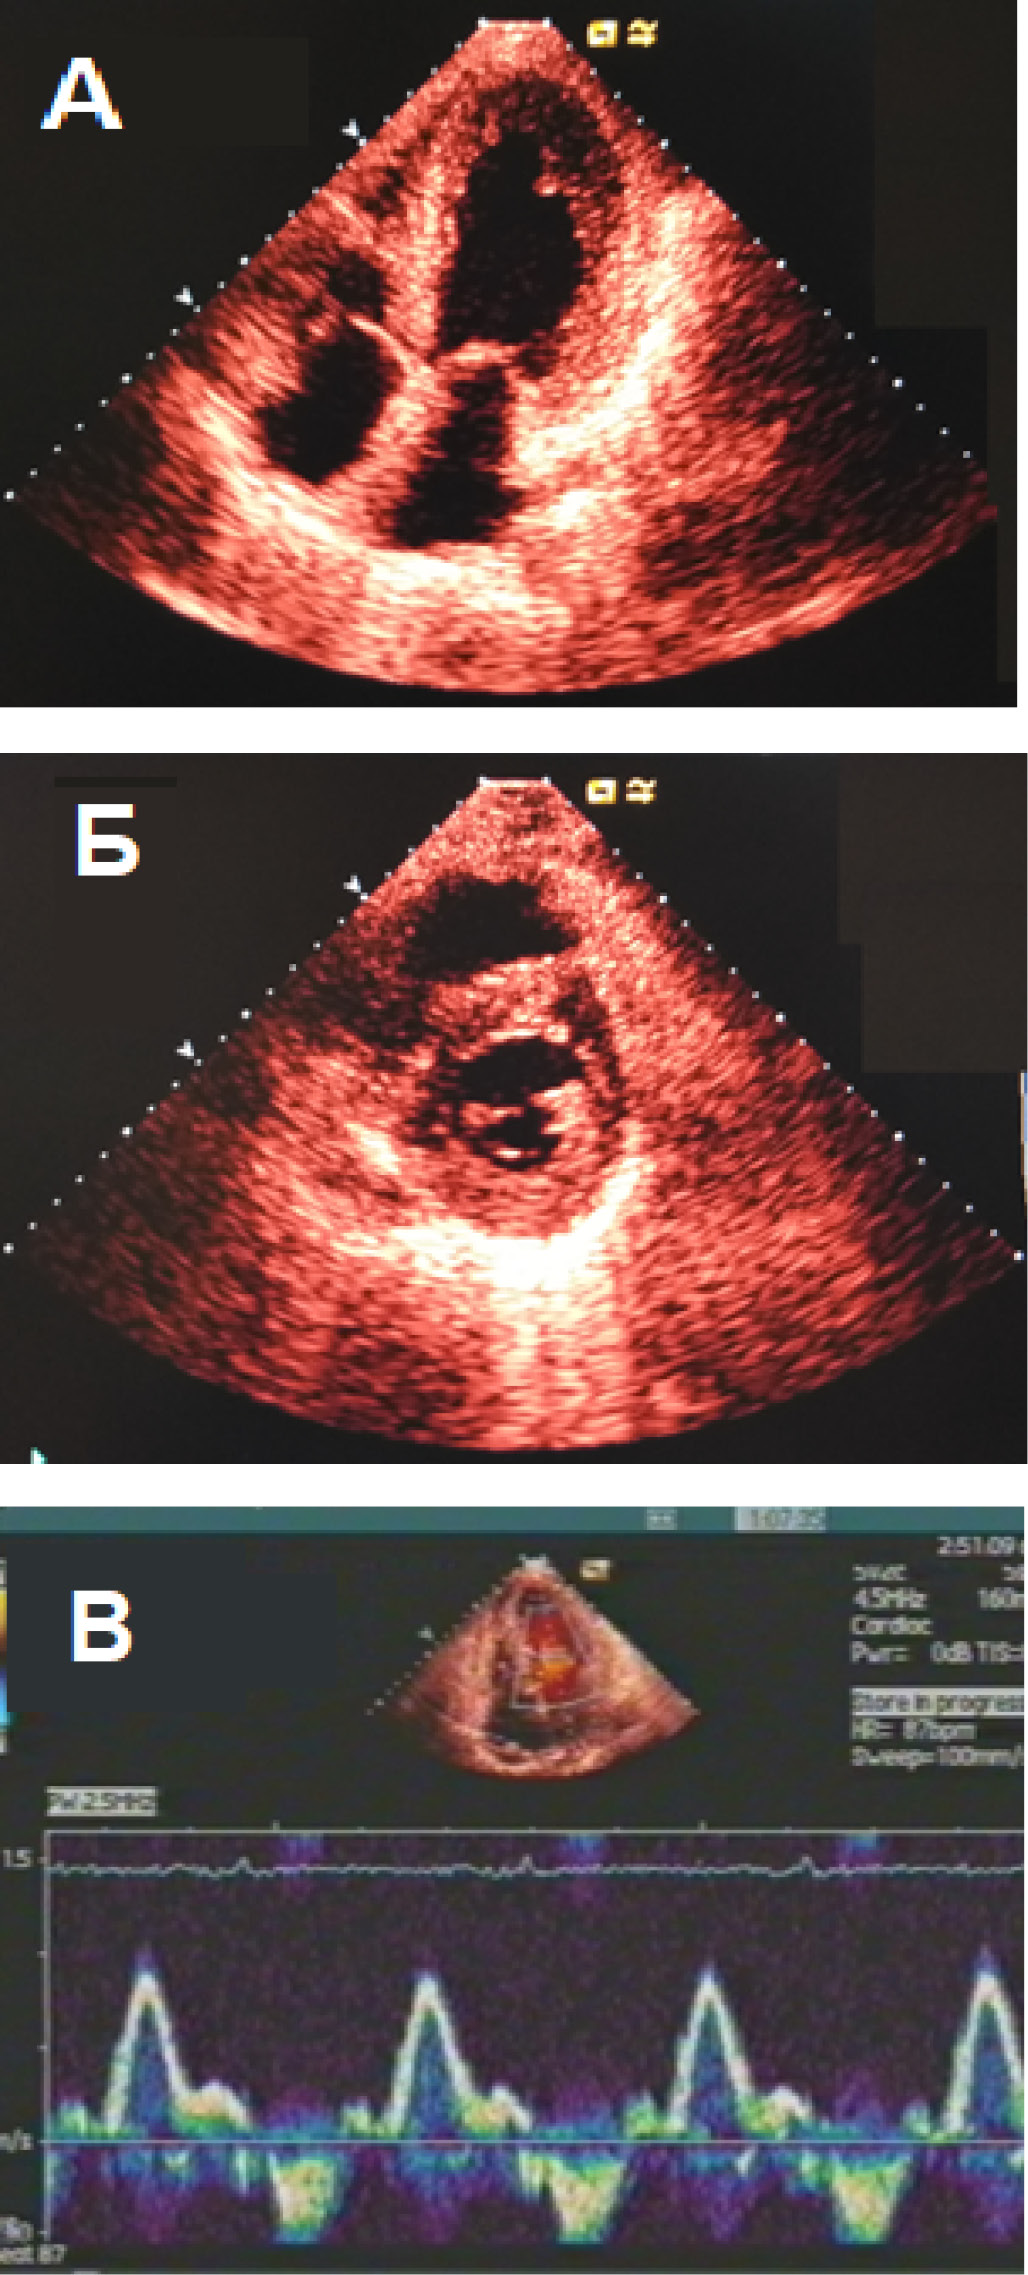

При эхокардиографическом исследовании (ЭхоКГ) признаками амилоидоза будет концентрическое утолщение миокарда ЛЖ (редко – асимметричное утолщение МЖП) с развитием ДД при небольшом размере полости. Связано это с тем, что депозиты амилоида больше всего откладываются в стенке ЛЖ и МЖП, но также и в правом желудочке. Соотношение пиков в раннюю и позднюю фазы диастолического наполнения значительно повышено (рестриктивный тип): E/A>1,5, укорачивается время замедления кровотока в период раннего наполнения ЛЖ(DT)<120 мс, а также время изоволюметрического расслабления ЛЖ (рис. 2). Значимо снижается соотношение систолического и диастолического венозных потоков в устьях легочных вен и растет скорость реверсивного потока в ЛП.

Рис 2. Эхокардиограмма больного AL-амилоидозом, выраженная псевдогипертрофия ЛЖ.

А – четырехкамерная позиция от верхушки, Б – короткая ось сердца на уровне папиллярных мышц в парастернальной позиции, В – импульсный трансмитральный допплер с рестриктивным типом диастолической дисфункции.